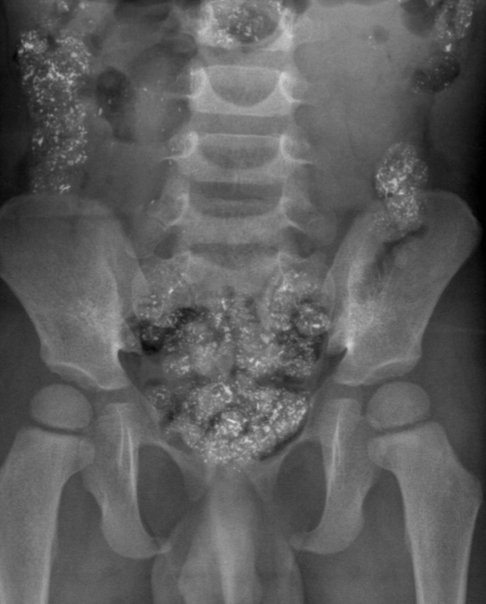

G. Patrick Daubert, MD

A 2-year-old African American boy was brought for evaluation of symptoms of an upper respiratory tract infection and intermittent abdominal pain.